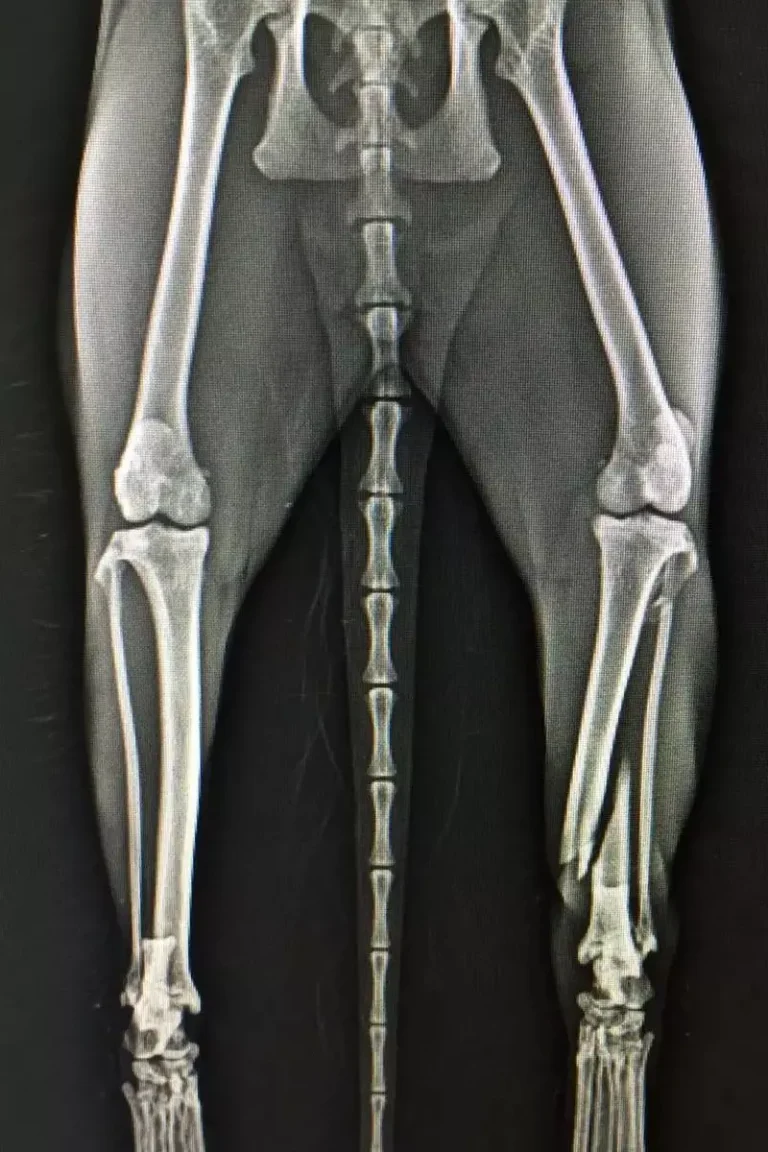

Evcil hayvanlar, yaşamları boyunca çeşitli nedenlerden dolayı iskelet ve kas sistemi sorunları yaşayabilirler. Bu sorunlar, kemik kırıkları, çıkıklar, eklem problemleri ve tendon yaralanmaları gibi çeşitli şekillerde ortaya çıkabilir. Bu tür durumlarda, cerrahi müdahale sıklıkla gereklidir.

Evcil hayvanların iskelet ve kas sistemi cerrahisi, veteriner hekimler tarafından yürütülen bir tedavi yöntemidir. Cerrahi müdahaleler, genellikle hayvanın anestezi altında tutulmasıyla gerçekleştirilir. Bu işlem, hayvanın ağrısını ve stresini azaltmak için gerekli olabilir.

Kemik kırıkları ve çıkıklar, evcil hayvanların en yaygın iskelet ve kas sistemi sorunlarıdır. Bu tür durumlarda, cerrahi müdahale, kemiklerin tekrar birleştirilmesi veya çıkarılması yoluyla gerçekleştirilir. Cerrahi müdahale sonrası, hayvanın bacaklarına alçı uygulanabilir veya splint adı verilen bir cihaz kullanılabilir. Bu cihazlar, hayvanın kemiklerin iyileşmesi sırasında doğru şekilde hizalanmasını sağlar.

Eklem sorunları, genellikle yaşlı evcil hayvanlarda görülen bir sorundur. Bu tür durumlarda, cerrahi müdahale ile eklemdeki hasarlı dokular çıkarılabilir veya eklem protezi yapılabilir. Bu tür işlemler, hayvanın eklem hareketliliğini geri kazanmasını sağlar.

Tendon yaralanmaları, evcil hayvanların kas sistemi sorunlarından bir diğeridir. Bu tür durumlarda, cerrahi müdahale ile yaralı tendon tamir edilir veya hasarlı tendon çıkarılır ve yeni bir tendon grefti yerleştirilir.